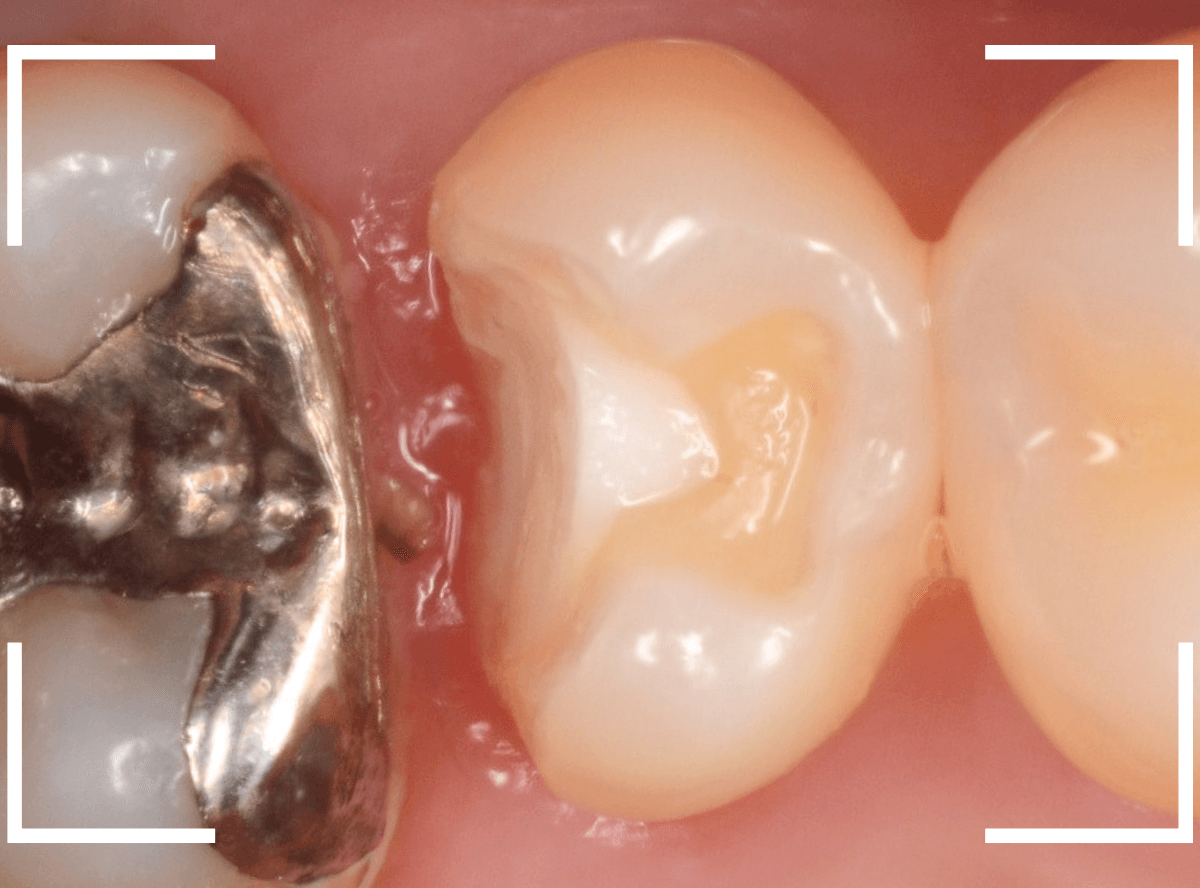

まず、慎重に金属を除去します。

金属の下に敷いてあったセメントも劣化しているのが分かりますので、そちらも除去して調べます。

セメントも除去したところです。

両歯とも、とても大きな虫歯なのがわかります。

慎重に虫歯を除去したところで、染色液で虫歯が除去できたか調べます。

まだうっすら虫歯が残っているのが分かります。

ほぼ全ての虫歯を除去したところです。

どちらの歯も神経ギリギリまで虫歯が進行していました。